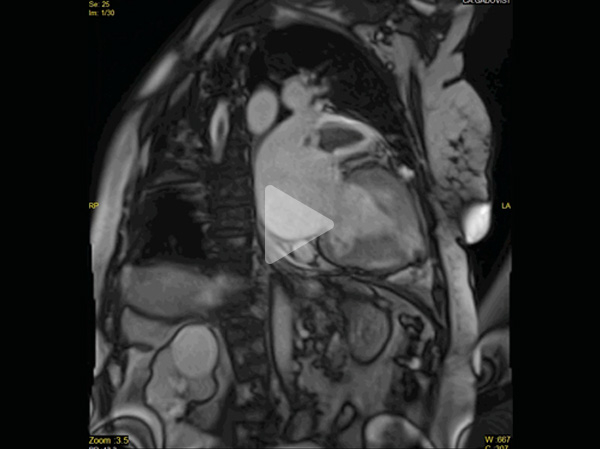

Vidéos 3 et 4 : Petite cavité VG, oreillettes dilatées - Anévrysme apical - Thrombus apex et auricule

Vidéo 3

Vidéo 4

B : post-gadolinium

Figure 5 : réhaussement tardif transmural apical et sous-endocardique latéral